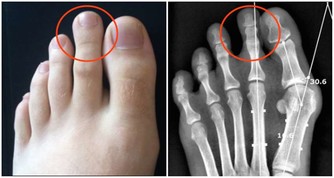

黃慧娟中醫師表示,馬齒莧屬性甘、酸、寒,具有清熱解毒、消炎止痛和活血消腫的作用,可用於治療泌尿道感染、便秘、青春痘、癰瘡腫毒、濕疹和女性白帶。另外,馬齒莧對於熱性腹瀉,例如細菌感染引發的拉肚子,也有不錯的改善效果;熱性腹瀉的症狀為肛門熱脹痛、排泄物呈稀黃狀。

中醫認為馬齒莧屬性甘、酸、寒,具有清熱解毒、消炎止痛和活血消腫的作用。